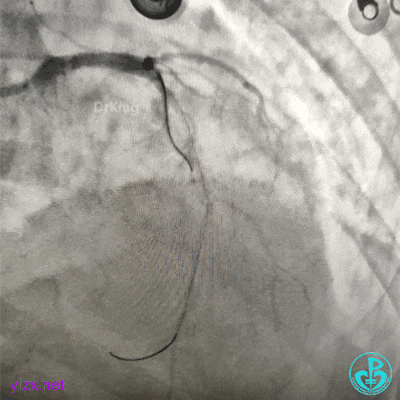

果断更换指引导管。

指引导管刚刚送到升主动脉,患者便发生抽搐、呼之不应,立即胸外按压几次后,患者清醒了,快速置入IABP。造影发现整个前壁不怎么搏动了。

交换导丝后扩支架网眼。

结束手术。

下台时血压127/78mmHg,心率75次/分。